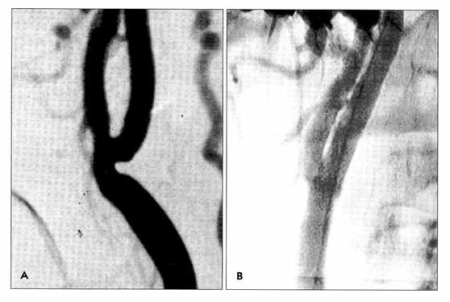

Karotidna restenoza na samoj bifurkaciji, glatke površine (A), Restenoza je rešena plasiranjem stenta.

Restenoza karotidne bifurkacije nakon PTA dilatacije sa stenom. Vađenje restenoziranog stenta uz zaštitu intraluminalnim shuntom